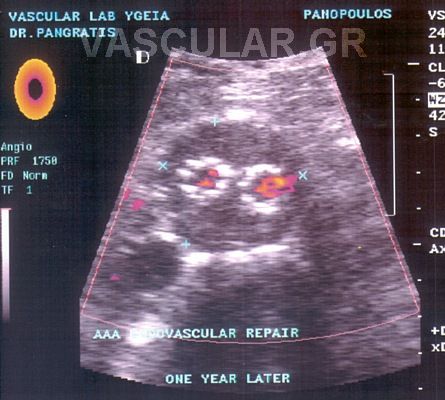

2. Ç åíäáããåéáêÞ áíôéìåôþðéóç êáôÜ ôçí ïðïßá ôïðïèåôåßôáé áðü ôçí ìçñéáßá áñôçñßá åíôüò ôïõ áõëïý ôïõ áíåõñýóìáôïò , åíäáõëéêüò íÜñèçêáò (stent) åðåíäåäõìÝíïò ìå åéäéêü õëéêü ãéá áðïêëåéóìü ôïõ áíåõñýóìáôïò.

Ç ôå÷íéêÞ áõôÞ åéóÞ÷èç êáé Ýãéíå ãéá ðñþôç öïñÜ óôçí ÅëëÜäá óôï íïóïêïìåßï «YÃEIA» áñ÷Ýò ôïõ 1995 áðü ôçí ïìÜäá åíäáããåéáêÞò ÷åéñïõñãéêÞò (Ð.ÌðÜëáò, Í.ÐáãêñÜôçò) êáé åîáêïëïõèåß íá ãßíåôáé ìå Üñéóôá áðïôåëÝóìáôá.

H äéÜñêåéá ôçò åðÝìâáóçò åßíáé 100 +- 30 ëåðôÜ êáé ï ÷ñüíïò ðáñáìïíÞò óôï íïóïêïìåßï åßíáé 3-4 çìÝñåò .

Ç áíôéìåôþðéóç ôïõ áíåõñýóìáôïò êïéëéáêÞò áïñôÞò äé åíäáããåéáêÞò ÷åéñïõñãéêÞò áðïôåëåß ìÝèïäï ãéá åðéëåãìÝíïõò áóèåíåßò , áóèåíåßò õøçëïý êéíäýíïõ êáé ðïõ äåí èá çäýíáíôï íá ÷åéñïõñãçèïýí ìå ôçí êëáóéêÞ ìÝèïäï .

Åí ôïýôïéò ìå ôçí áðïêôçèåßóá äéåèíÞ êáé çìåôÝñá åìðåéñßá ïé åíäåßîåéò åêôÝëåóçò ôçò íÝáò áõôÞò ìåèüäïõ äéåõñýíïíôáé þóôå íá ðåñéëáìâÜíåé áóèåíåßò íåùôÝñáò çëéêßáò êáé óå êáëÞ ãåíéêÞ êáôÜóôáóç.

Ïé ÅíäáããåéáêÝò åðåìâÜóåéò óå áíåýñõóìá ôçò êïéëéáêÞò áïñôÞò (ÁÊÁ) õðåñôåñïýí ôçò êëáóóéêÞò åã÷åéñÞóåùò êáè üóïí ãßíåôáé äé åëá÷ßóôïõ ôñáýìáôïò, ç ðáñáìïíÞ ôïõ áóèåíïýò óôï íïóïêïìåßï åßíáé âñá÷åßá, áðïöåýãïíôáé ïé óåîïõáëéêÝò äéáôáñá÷Ýò óå Üíäñåò êáé ç åðÜíïäïò óôéò êáèçìåñéíÝò åíáó÷ïëßåò åßíáé ôá÷ýôáôç.

Ç éäÝá ôçò áðïêáôÜóôáóçò ôïõ áíåõñýóìáôïò ÷ùñßò áðïêÜëõøç êáé áðïêëåéóìü ôçò áïñôÞò èåùñåßôáé üôé ìðïñåß áêüìç íá ìåéþóåé ôçí íïóçñüôçôá êáé ôçí èíçôüôçôá. Åôóé õðÜñ÷åé óõíå÷Þò åîÝëéîç ìå ôçí ÷ñçóéìïðïéïýìåíç ôå÷íéêÞ áíÜðôõîç êáé äïêéìáóßá íÝùí óõóôçìÜôùí , åê ôùí ïðïßùí ôá ðåñéóóüôåñá åìöáíßæïíôáé áðïôåëåóìáôéêÜ óôïí áðïêëåéóìü ôïõ áíåõñýóìáôïò áðü ôçí êõêëïöïñßá .